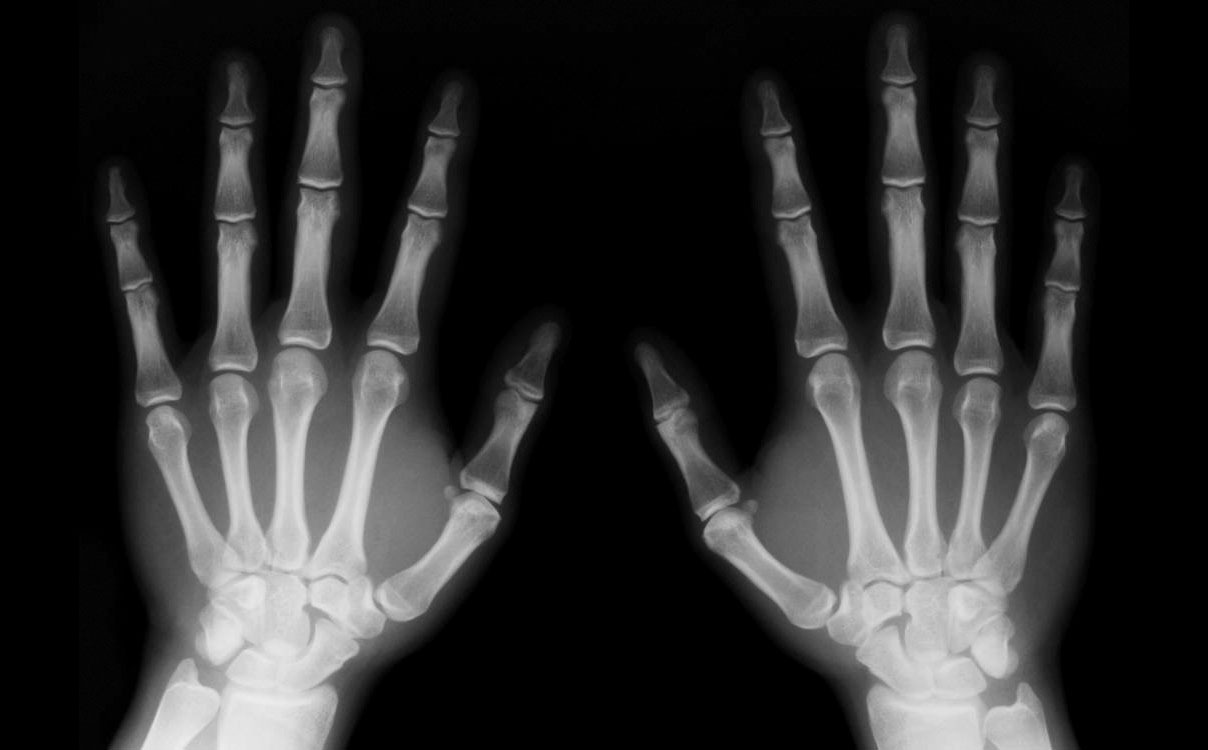

Existen muchas de estas herramientas, aunque una de las más conocidas por la población en general son los rayos X; pues, por un motivo u otro, más o menos todos hemos tenido que someternos a ellos en algún momento de nuestras vidas. Y precisamente son éstos los que podrían ser sustituidos por una nueva técnica, desarrollada por científicos del Trinity College de Dublin.

Aunque, como os decía, se trata de un método muy extendido por haber demostrado ser de gran eficacia, el diagnóstico por imagen con rayos X conlleva una serie de inconvenientes, como posibles problemas para la salud del paciente o baja eficacia en el estudio de la calidad de los huesos.

Esto se debe a que, si bien es cierto que son muy útiles para detectar fracturas y otras variaciones en la densidad de los huesos, para poder obtener otros datos igualmente importantes sería necesario de una imagen tridimensional y a escala nanométrica, en la que se pudieran localizar problemas imperceptibles a través de los métodos rutinarios.